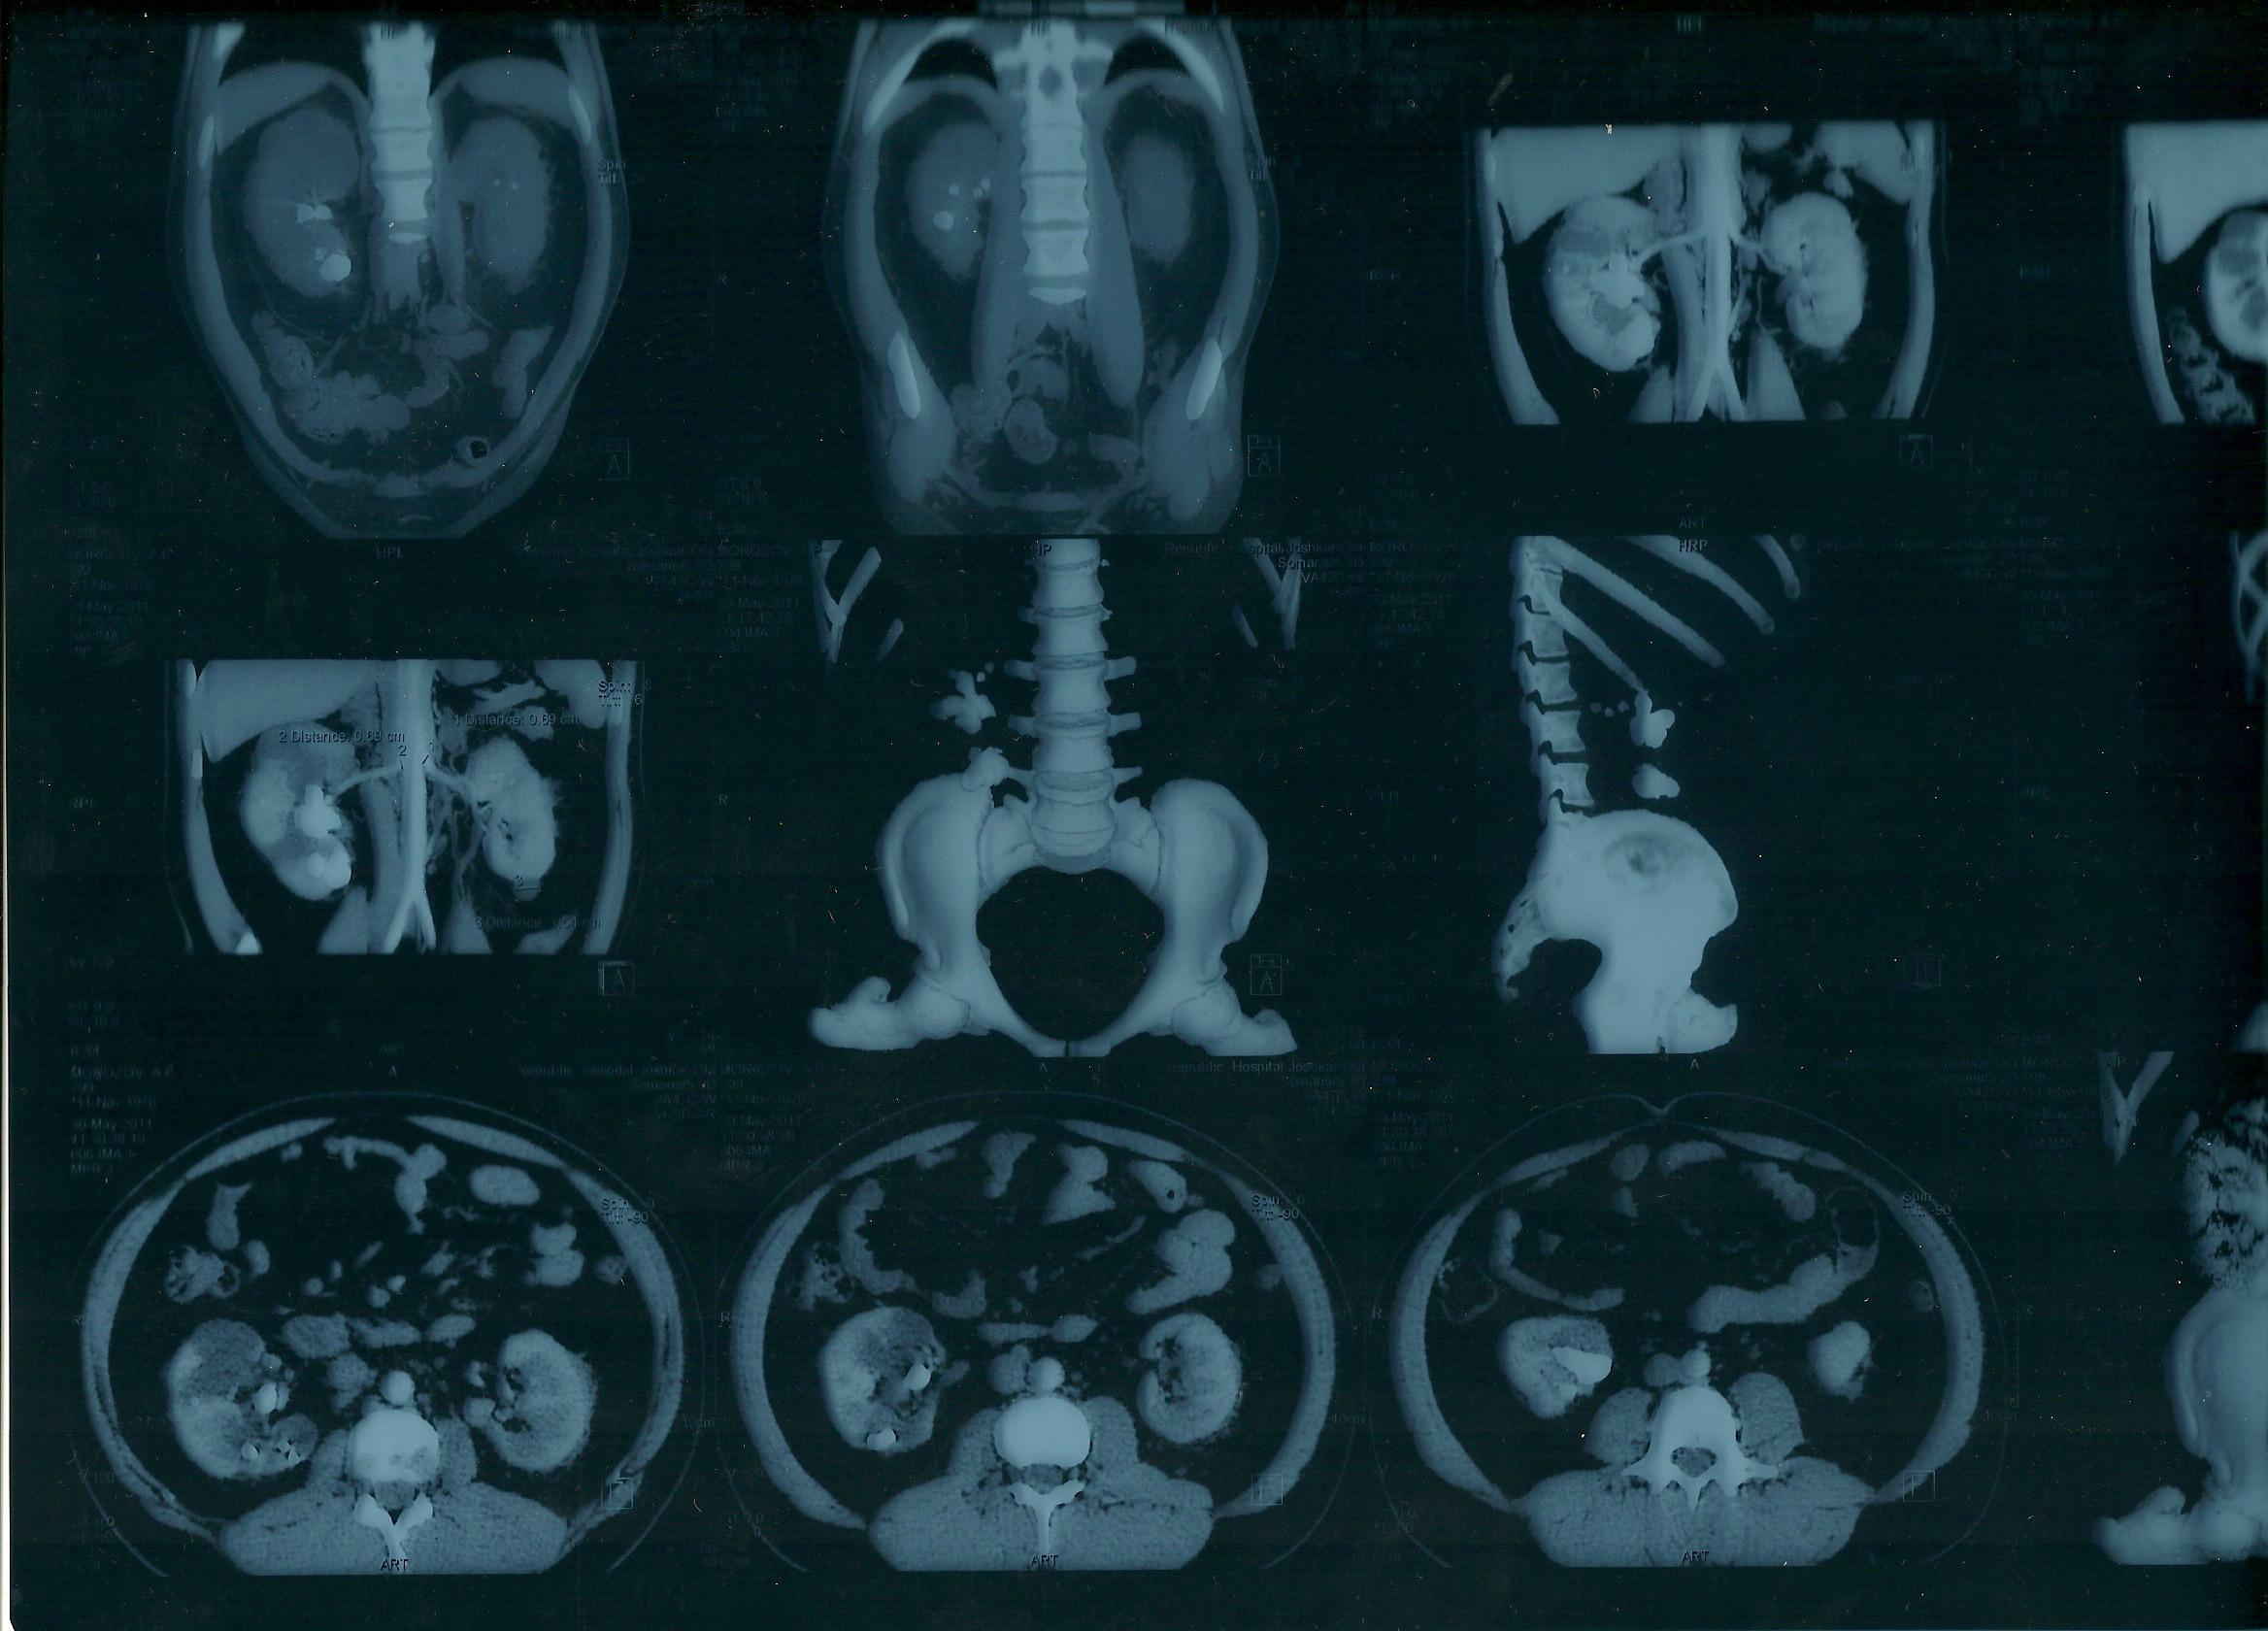

коралловидный камень

Морозов Алексей. Здравствуйте,находился

на лечении в урологическом отделении

г.Йошкар-Ола по поводу МКБ, В правой почке

обнаружен коралловидный камень,врач

рекомендовал ЧПНЛ в Нижнем Новгороде,но